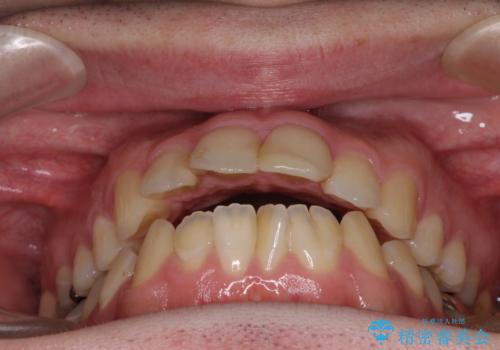

- 口がうまく閉じられないとのことで来院された患者様です。

上下唇をしっかり合わせようとすると、顎先が前方に突出してしまうほど口が閉じにくい状態でした。

口元の突出感を改善するために上下左右の第一小臼歯4本を抜歯し、ワイヤー装置にて矯正治療を行うこととしました。

また、上下前歯は舌の突出癖による開咬となっていたため、舌のトレーニングを徹底するよう指示しました。